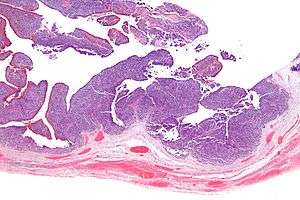

| Micrograph of transitional cell carcinoma of the ovary. H&E stain. | |

TCC of the ovary is diagnosed by examination of the tissue by a pathologist. It has a characteristic appearance under the microscope and distinctive pattern of immunostaining.[2]